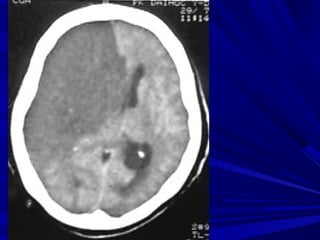

Buøi vaên L., Nam, 45 tuoåi, Xuaát huyeát nhaân beøo-bao trong (P) coù

traøn maùu naõo thaát

Buøi Vaên L., Nam, 45 tuoåi, Xuaát huyeát nhaân